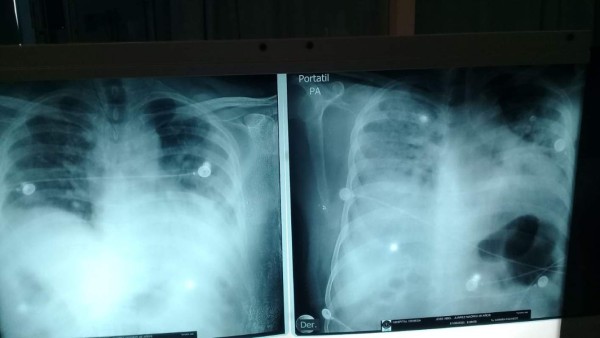

La radiografía muestran los pulmones de un paciente del hospital Leonardo Martínez. La imagen de la derecha cuando el paciente llegó al hospital, la izquierda luego de aplicar el Catracho.